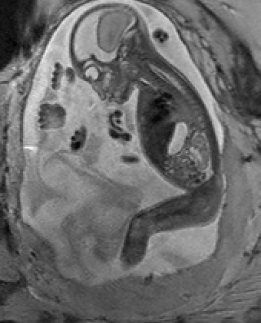

During image acquisition the fetus is not sedated and moves freely as well as the mother breathes normally. As a result, movements are likely to corrupt the scans, hiding pathology and causing overlap between different anatomical regions. In order to limit these artifacts, fast scanning sequences such as ssFSE [10] allow for the rapid acquisition of single slices at high in-plane resolution in a large field of view and good tissue contrast of the uterus. However, when acquiring a 3D volume through a stack of slices, inter-slice artifacts in the out-of-plane views are highly likely. Consequently, this restricts reliable diagnostics to individual slices in the current clinical practice. Fig. 1 depicts a typical example of motion related artifacts in a fetal single-shot fast spin echo (ssFSE) scan. The observed motion (c.f. Fig. 1 b & c) is of unpredictable nature and consists of a combination of maternal respiration movements, fetal movements and bowel movements.

Reconstruction of Fetal Organs: Exemplary PVR and SVR reconstructions under motion introduced by kicking of the fetus are shown in Fig. 11. PVR reconstruction results show an improved visual appearance and less blurring in the region with severe motion artifacts (arrow). An example of a challenging clinical case with a kidney malformation in one of twin fetuses, is shown in Fig. 8. Our clinical partners confirmed that such complications are easier to examine and to quantify after PVR-based reconstruction.